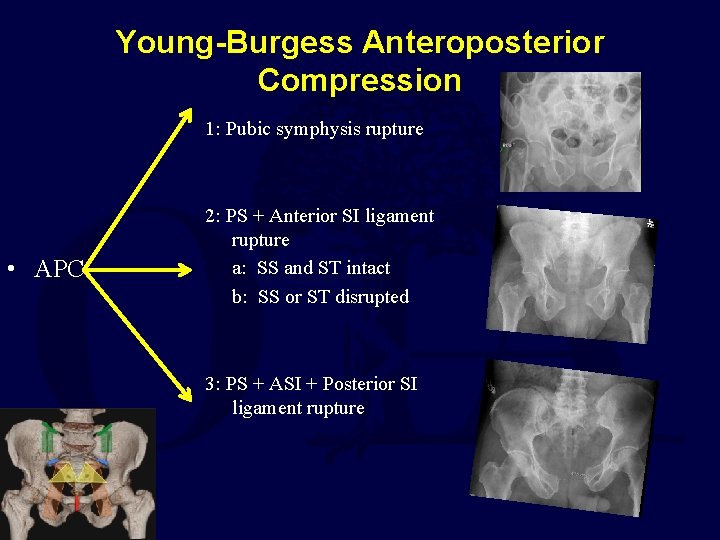

Young-Burgess Anteroposterior Compression 1: Pubic symphysis rupture • APC 2: PS + Anterior SI ligament rupture a: SS and ST intact b: SS or ST disrupted 3: PS + ASI + Posterior SI ligament rupture